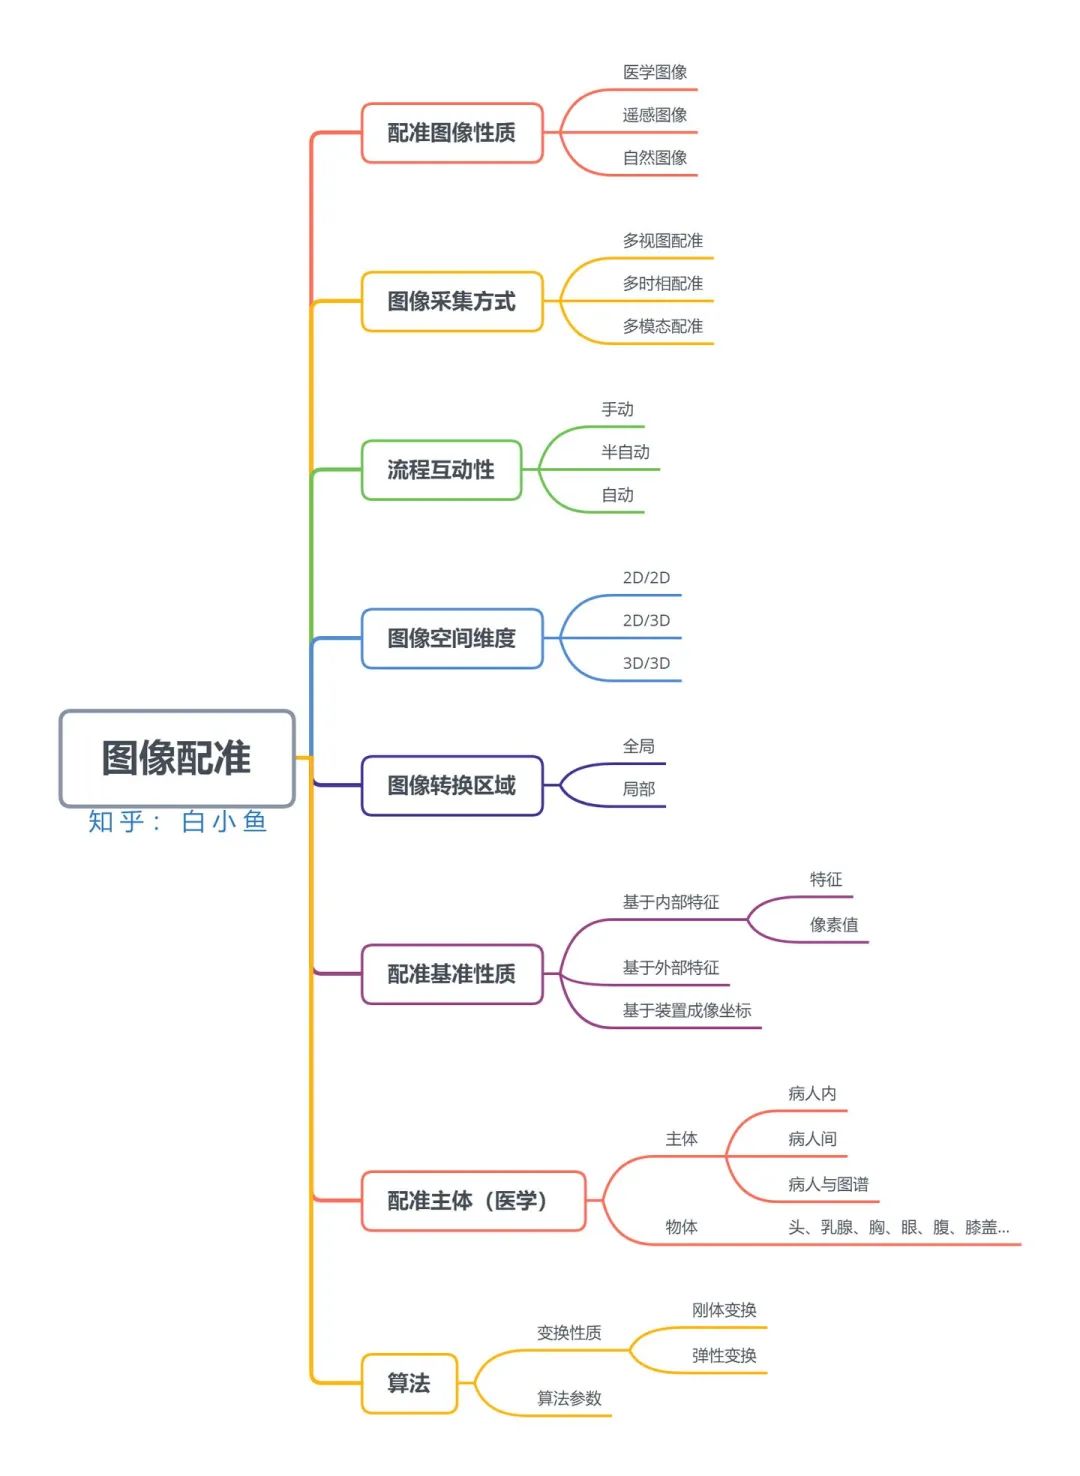

图像配准分类标准不唯一,下面两图是某位研究者的分类结果(2014年)。

笔者依照自己的理解做了如下的分类:

根据问题特点的分类:

1. Registration Quality: 配准性质

根据数据或特征确定的配准类型。

如自然图像配准,医学图像配准,遥感图像配准等。

2. 图像采集方式

① Multi-view Analysis: 多视图配准

同一物体在同一场景不同视角下的图像配准。

从多个视角捕获相似对象或场景的图像,以便获得扫描对象或场景的更好表示。如使用图像拼接,从2D图像重建3D模型等。

②Multi-temporal Analysis: 多时相配准

同一物体在同一场景同视角不同时间的图像配准。如运动追踪,肿瘤生长情况跟踪等。

③Multi-modal Analysis: 多模态配准

多模配准常见于医学图像领域,故以多模医学图像配准为例。

由于医学成像设备可以提供关于患者不同信息不同形式的图像(计算机断层扫描CT,核磁共振MRI,正电子发射断层成像PET,功能核磁共振fMRI等)。

基于单种或多种模态图像的配准,可划分为单模态(Single-modality)和多模态(Multi-modality)。

3. Interaction: 配准流程互动性

手动,半自动或自动

4. Dimensionality: 图像空间维数

若仅考虑空间维数,可以划分为2D/2D, 2D/3D, 3D/3D等。若考虑时间序列因素,还存在对在不同时刻提取的两幅图像进行配准的问题。

5. Domain of transformation: 图像转换区域(全局/局部配准)

6. Nature of Registration basis: 配准基准的性质

根据算法所基于的特征及相似性测度。

①基于内部特征的配准

内部特征指的是从图像内部本身提取的信息。

基于特征(feature-based):在几何上有特别意义的可以定位的特征点集(比如不连续点,图形的转折点,线交叉点等),或者用分割的方法提取出感兴趣的部分的轮廓(曲线或曲面),以作为用来比较的特征空间。在医学图像上可以是具有解剖意义的点。

基于像素值(intensity-based):利用整幅图像的像素或体素来构成特征空间。根据像素值的统计信息来计算相似性测度又可划分为最小二乘法,傅里叶法,互相关法,互信息法等等。

②基于外部特征的配准

在医学图像中,通过在患者身上固定标记物或向体内注入显影物质以获得在图像上的确定的标记点,称为外部特征点。

③基于不同装置成像坐标的配准

7. Subject of Registration: 配准主体

以医学图像配准为例,可分为 Intra-subject (图像来自于同一病人),Inter-subjective (来自不同的病人)和 Atlas (病人数据和图谱的配准)三种。

Object of Registration 配准物体:头、乳腺、胸、眼、腹、膝盖 等…

8. Type of transformation: 变换性质

根据用于将浮动图像空间与参考图像空间相关联的变换模型对图像配准算法进行分类。对图像进行空间变换可以分为刚体变换(rigid)和非刚体变换(non- rigid, deformable)。

第一类变换模型是线性变换,包括旋转,缩放,平移和其他仿射变换。线性变换本质上是全局的,因此,它们无法模拟图像之间的局部几何差异。

第二类变换模型允许“弹性”或“非刚性”变换。这些变换能够局部地扭曲浮动图像使其与参考图像对准。非刚性变换包括径向基函数(薄板或曲面样条函数,多重二次曲面函数和紧支撑变换),物理连续模型(粘性流体)和大变形模型(微分同胚)。

变换模型通常是参数化的例如,可以通过单个参数(变换向量)来描述整个图像的变换。这些模型称为参数模型。另一方面,非参数模型不遵循任何参数化,允许每个图像元素任意移位。

9. Parameters of Registration: 算法参数

当比较特征采用特征点集的形式时,可以通过联立方程组来找到变换的解。

但一般情况下,配准问题都会转化为求解相似性测度最优值的问题,在计算方法中通常需要采用合适的迭代优化算法,诸如梯度下降法、牛顿法、Powell法、遗传算法等。